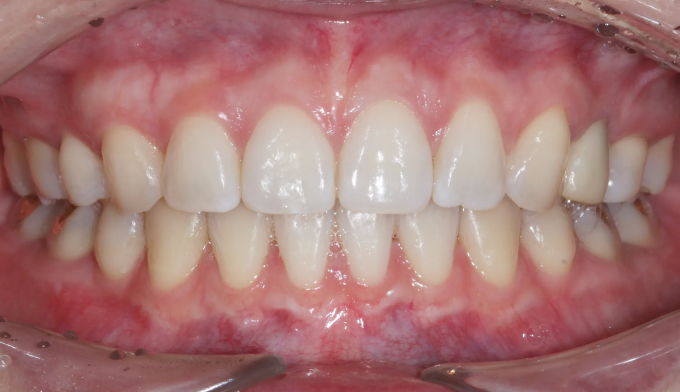

전에 교정치료를 마무리하고 지내던 중 치아 안쪽에 붙여놓은 유지장치가 떨어지면서 관리를 못하게 된 경우입니다. 이런 경우 앞니가 다시 틀어지거나 벌어질 수 있습니다.

위 유지장치는 모두 제거되어보이고, 아래 유지장치 또한 양 끝이 끊어져서 치아사이가 벌어져 보입니다.

서비스직에서 일하고 있어 치아 안쪽으로 붙이는 설측교정을 원하였고, 9개월만에 교정치료 종료 하였습니다.

유지장치가 떨어지면서 벌어진 치아들과 깊어진 앞니들을 이상적인 위치로 배열시켰습니다.